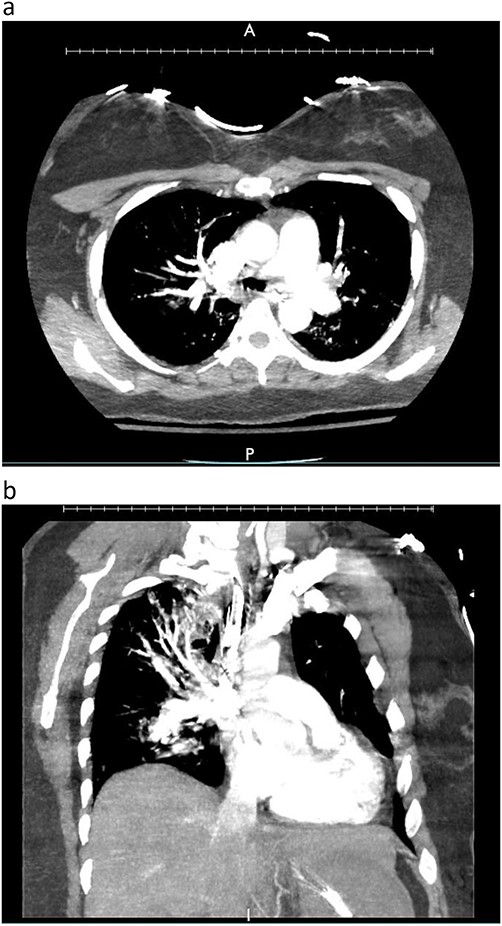

Postoperative graft CT scan: recipients had bilateral lung reduction due to over size.